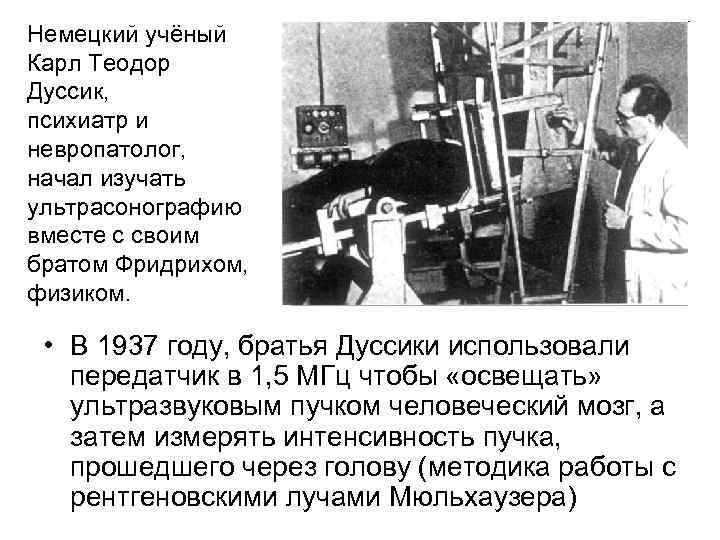

Немецкий учёный Карл Теодор Дуссик, психиатр и невропатолог, начал изучать ультрасонографию вместе с своим братом Фридрихом, физиком. • В 1937 году, братья Дуссики использовали передатчик в 1, 5 МГц чтобы «освещать» ультразвуковым пучком человеческий мозг, а затем измерять интенсивность пучка, прошедшего через голову (методика работы с рентгеновскими лучами Мюльхаузера)

Немецкий учёный Карл Теодор Дуссик, психиатр и невропатолог, начал изучать ультрасонографию вместе с своим братом Фридрихом, физиком. • В 1937 году, братья Дуссики использовали передатчик в 1, 5 МГц чтобы «освещать» ультразвуковым пучком человеческий мозг, а затем измерять интенсивность пучка, прошедшего через голову (методика работы с рентгеновскими лучами Мюльхаузера)